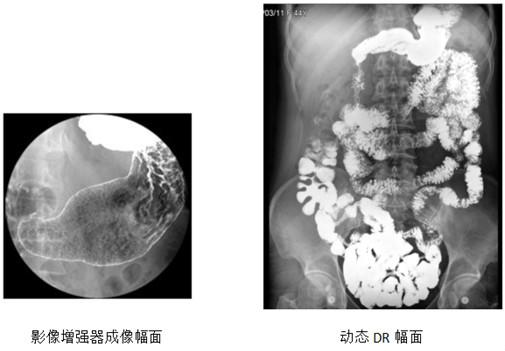

其次,以前的胃肠机采用的是影像增强器成像,图像视野小,会出现不可避免的枕形失真,对比度不均匀等问题。临床上输出的影像较为模糊,容易导致误诊、漏诊的发生。安健动态DR 与传统影像增强器成像比较,图像更清晰,视野更大,一张图像能覆盖整个胸部或腹部,成像面积为17"×17"大尺寸,能够采集更广阔矩形面积的动态图像。